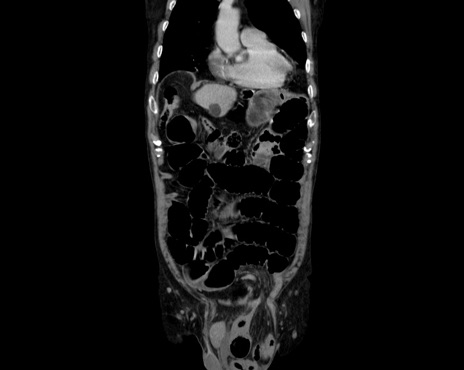

横断像